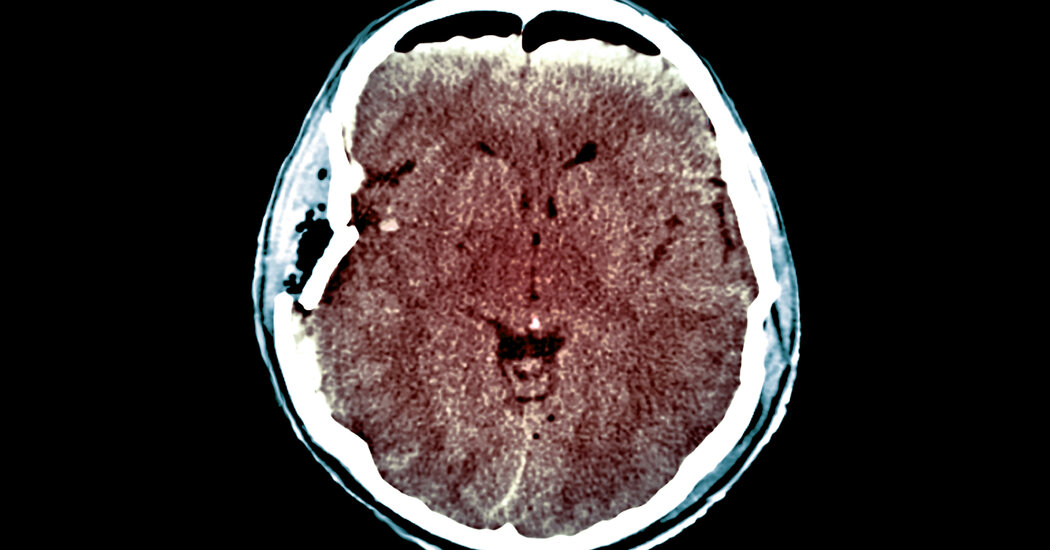

Nearly 100 neurology experts collaborated on the creation of a new method of evaluating patients with traumatic brain injuries.

But little has changed in the world of traumatic brain injuries since Dr. Manley’s patient woke up. Assessments of who will recover and how severely patients are injured are pretty much the same, which results in patients being told they “just” have a concussion, who then have trouble getting care for recurring symptoms like memory lapses or headaches. And it results in some patients in the position of that policemen, who have their life support withdrawn when they might have recovered.